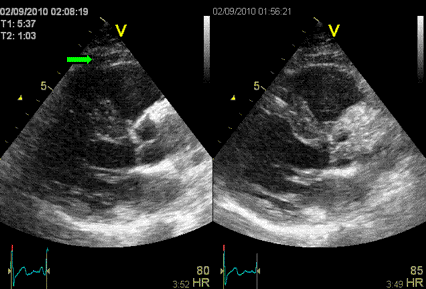

Ультразвуковое исследование (УЗИ)

Сегодня ультразвуковые исследования – нестареющая классика. Метод дает большое количество информации и относится к самым доступным и безопасным. УЗИ проводится для исследования плода, гинекологических, урологических, эндокринных, сосудистых и болезней ЖКТ. Работает УЗИ-аппарат следующим образом: он испускает звуковые волны и по отражению волн определяет границы, плотность и другие характеристики исследуемых органов.

Путь ультразвука (УЗ) в медицинскую диагностику был тернист. Долгое время ультразвук использовали для поиска дефектов в металле, а в медицину он изначально попал как лечебное физиотерапевтическое средство. В диагностических целях первый раз УЗ применил невролог Карл Дуссик. С его помощью доктор изучал структуры мозга у человека. Как это часто бывает, первый блин вышел комом: врач неверно интерпретировал результаты, сочтя кость черепа мягкой опухолью. Зато вторая попытка прошла вполне удачно. В 1949 г. Джон Уайлд с помощью УЗИ смог правильно оценить толщину стенок кишечника у своего пациента.

В случае УЗИ качество диагностики зависит и от аппарата, и от умений врача. Так, опытный специалист, используя систему последнего поколения, сможет заподозрить опухолевый процесс даже на самой начальной стадии. Из-за своей безвредности УЗИ активно применяется у детей и беременных и как дополнительный метод к другим, более «тяжелым» видам сканирования.